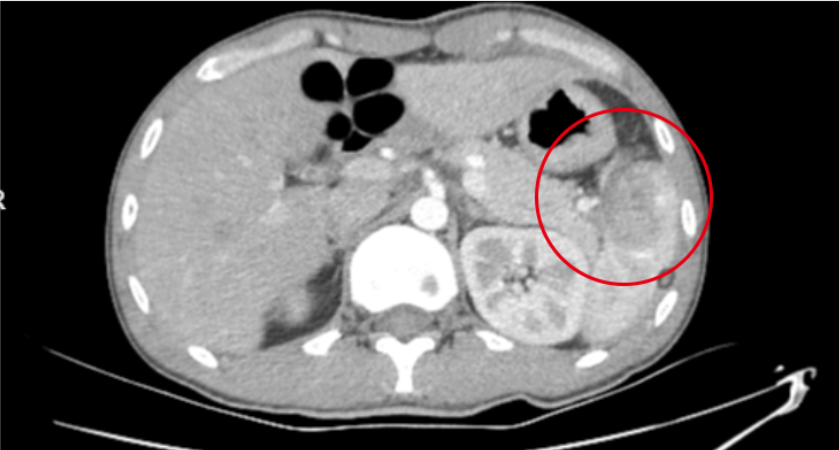

2025年5月31日清晨,23岁的李先生(化名)因骑电动车不慎摔倒导致左侧季肋区受伤、创伤性脾破裂,失血性休克。经我院创伤中心团队紧急施救,成功实施脾修补手术。